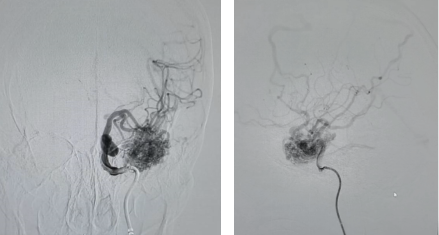

术前DSA

王女士2年前因癫痫发作,在外院检查发现颅内存在较大畸形血管团,供血及引流血管情况复杂,因惧怕手术风险,一直未接受手术治疗。4天前,王女士突发头痛,伴有频繁恶心呕吐,无法行走,意识反应逐渐下降,随后被紧急送至我院急诊医学科。经头颅CT检查,提示脑室出血、脑肿胀、左侧颞叶稍高密度影、点状钙化灶。面对患者脑室出血、畸形血管团较大等复杂状况,手术难度极大,风险高,术中脑血管畸形破裂出血的可能性大,甚至可能危及生命。神经外科二病区纪文军主任医师团队开展深入讨论,制定了详尽的手术方案,最终与患者及家属充分沟通后决定为其行介入栓塞术。

术中,在纪文军主任医师、张伟副主任医师、李涛副主任医师、赵乐副主任医师及麻醉手术科团队的紧密协作下,成功对王女士脑中的动静脉畸形多支供血血管进行了栓塞。手术历时两个多小时,顺利完成。术后复查脑血管造影显示,颅内动静脉畸形已完全栓塞。后期经过神经外科二病区医护团队精心的康复治疗与护理,王女士恢复良好,意识清晰,已能正常生活和工作。